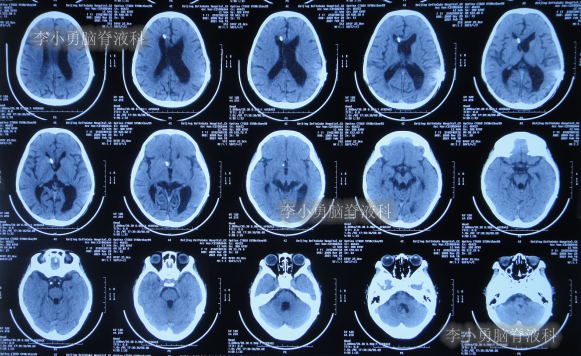

数天之后即在2013年9月2日,为治疗脑积水,患儿至河南省郑州市某三甲医院神经外科就诊,当日头颅CT示严重脑积水并第四脑室扩张严重(图-1);当天收入院。在住院后次日即2013年9月3日,进行了右侧额角脑室腹腔分流术。

图-1:2013年9月2 日头颅CT